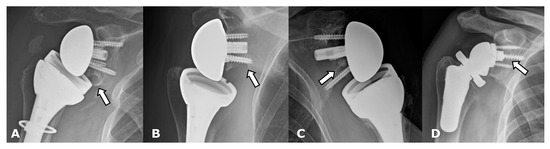

| Grade | Finding |

|---|---|

| 1 | Lucency extends to scapular pillar |

| 2 | Lucency contacts the inferior glenoid screw |

| 3 | Lucency extends over the inferior glenoid screw |

| 4 | Lucency extends under the metaglene/baseplate |

5.2. Reverse Arthroplasty

Reverse Total Shoulder Arthroplasty (RTSA)